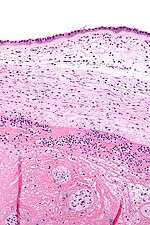

Micrograph showing chorioamnionitis. The clusters of blue dots are inflammatory cells (neutrophils, eosinophils and lymphocytes). H&E stain. | |

Chorioamnionitis can be diagnosed from a histologic examination of the fetal membranes.

Infiltration of the chorionic plate by neutrophils is diagnostic of (mild) chorioamnionitis. More severe chorioamnionitis involves subamniotic tissue and may have fetal membrane necrosis and/or abscess formation.

Severe chorioamnionitis may be accompanied by vasculitis of the umbilical blood vessels (due to the fetus' inflammatory cells) and, if very severe, funisitis (inflammation of the umbilical cord's connective tissue).